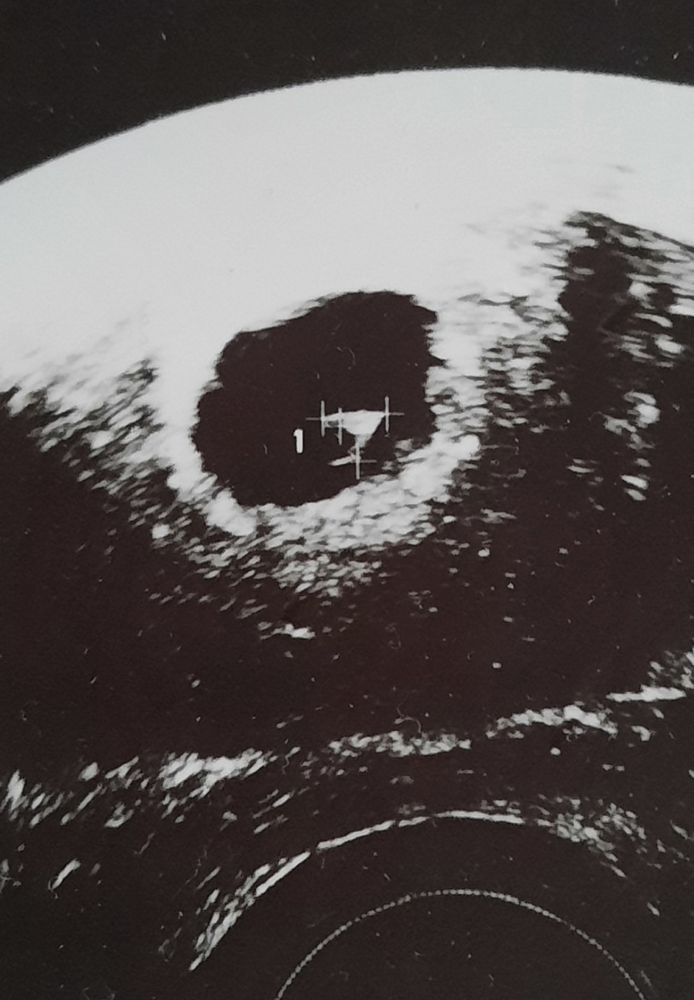

Результаты УЗИНаконец и я дождалась своего бриллиантика🥰 Первое узи на 21дпп моей пятидневочки🌸

ПЯ -13.1 мм

ЖМ - 3.4 мм

КТР - 2.9 мм

Сердцебиение определяется в виде пульсации.

Маточная беременность 5 недель и 6 дней 💕